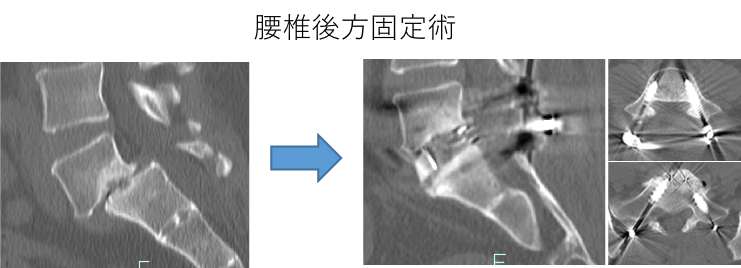

腰椎除圧術・固定術

腰椎椎間板ヘルニア、腰部脊柱管狭窄症、成人脊柱変形(側彎症、後彎症)、により坐骨神経痛などを代表とする下肢の神経症状が出現します。まずは内服薬による治療から開始しますが、痛みの症状が強い場合には硬膜外ブロックや神経根ブロックなどを行います。それでも症状が寛解しない場合には、筋層を温存してなおかつ効果が長く持続する棘突起縦割椎弓形成術から、側方から後腹膜腔を経由して脊椎の前方から固定を行う椎体置換術やOLIF、後方からのPLIF、TLIFなどの固定方法を患者さんごとに使い分けて最善の治療を目指します。

一般的に後方からスクリューで固定されてしまう外側型の腰椎椎間板ヘルニアについても、画像所見によっては、当科では外側からの除圧術のみで対応します。

腰椎後方固定術 腰椎椎体置換術